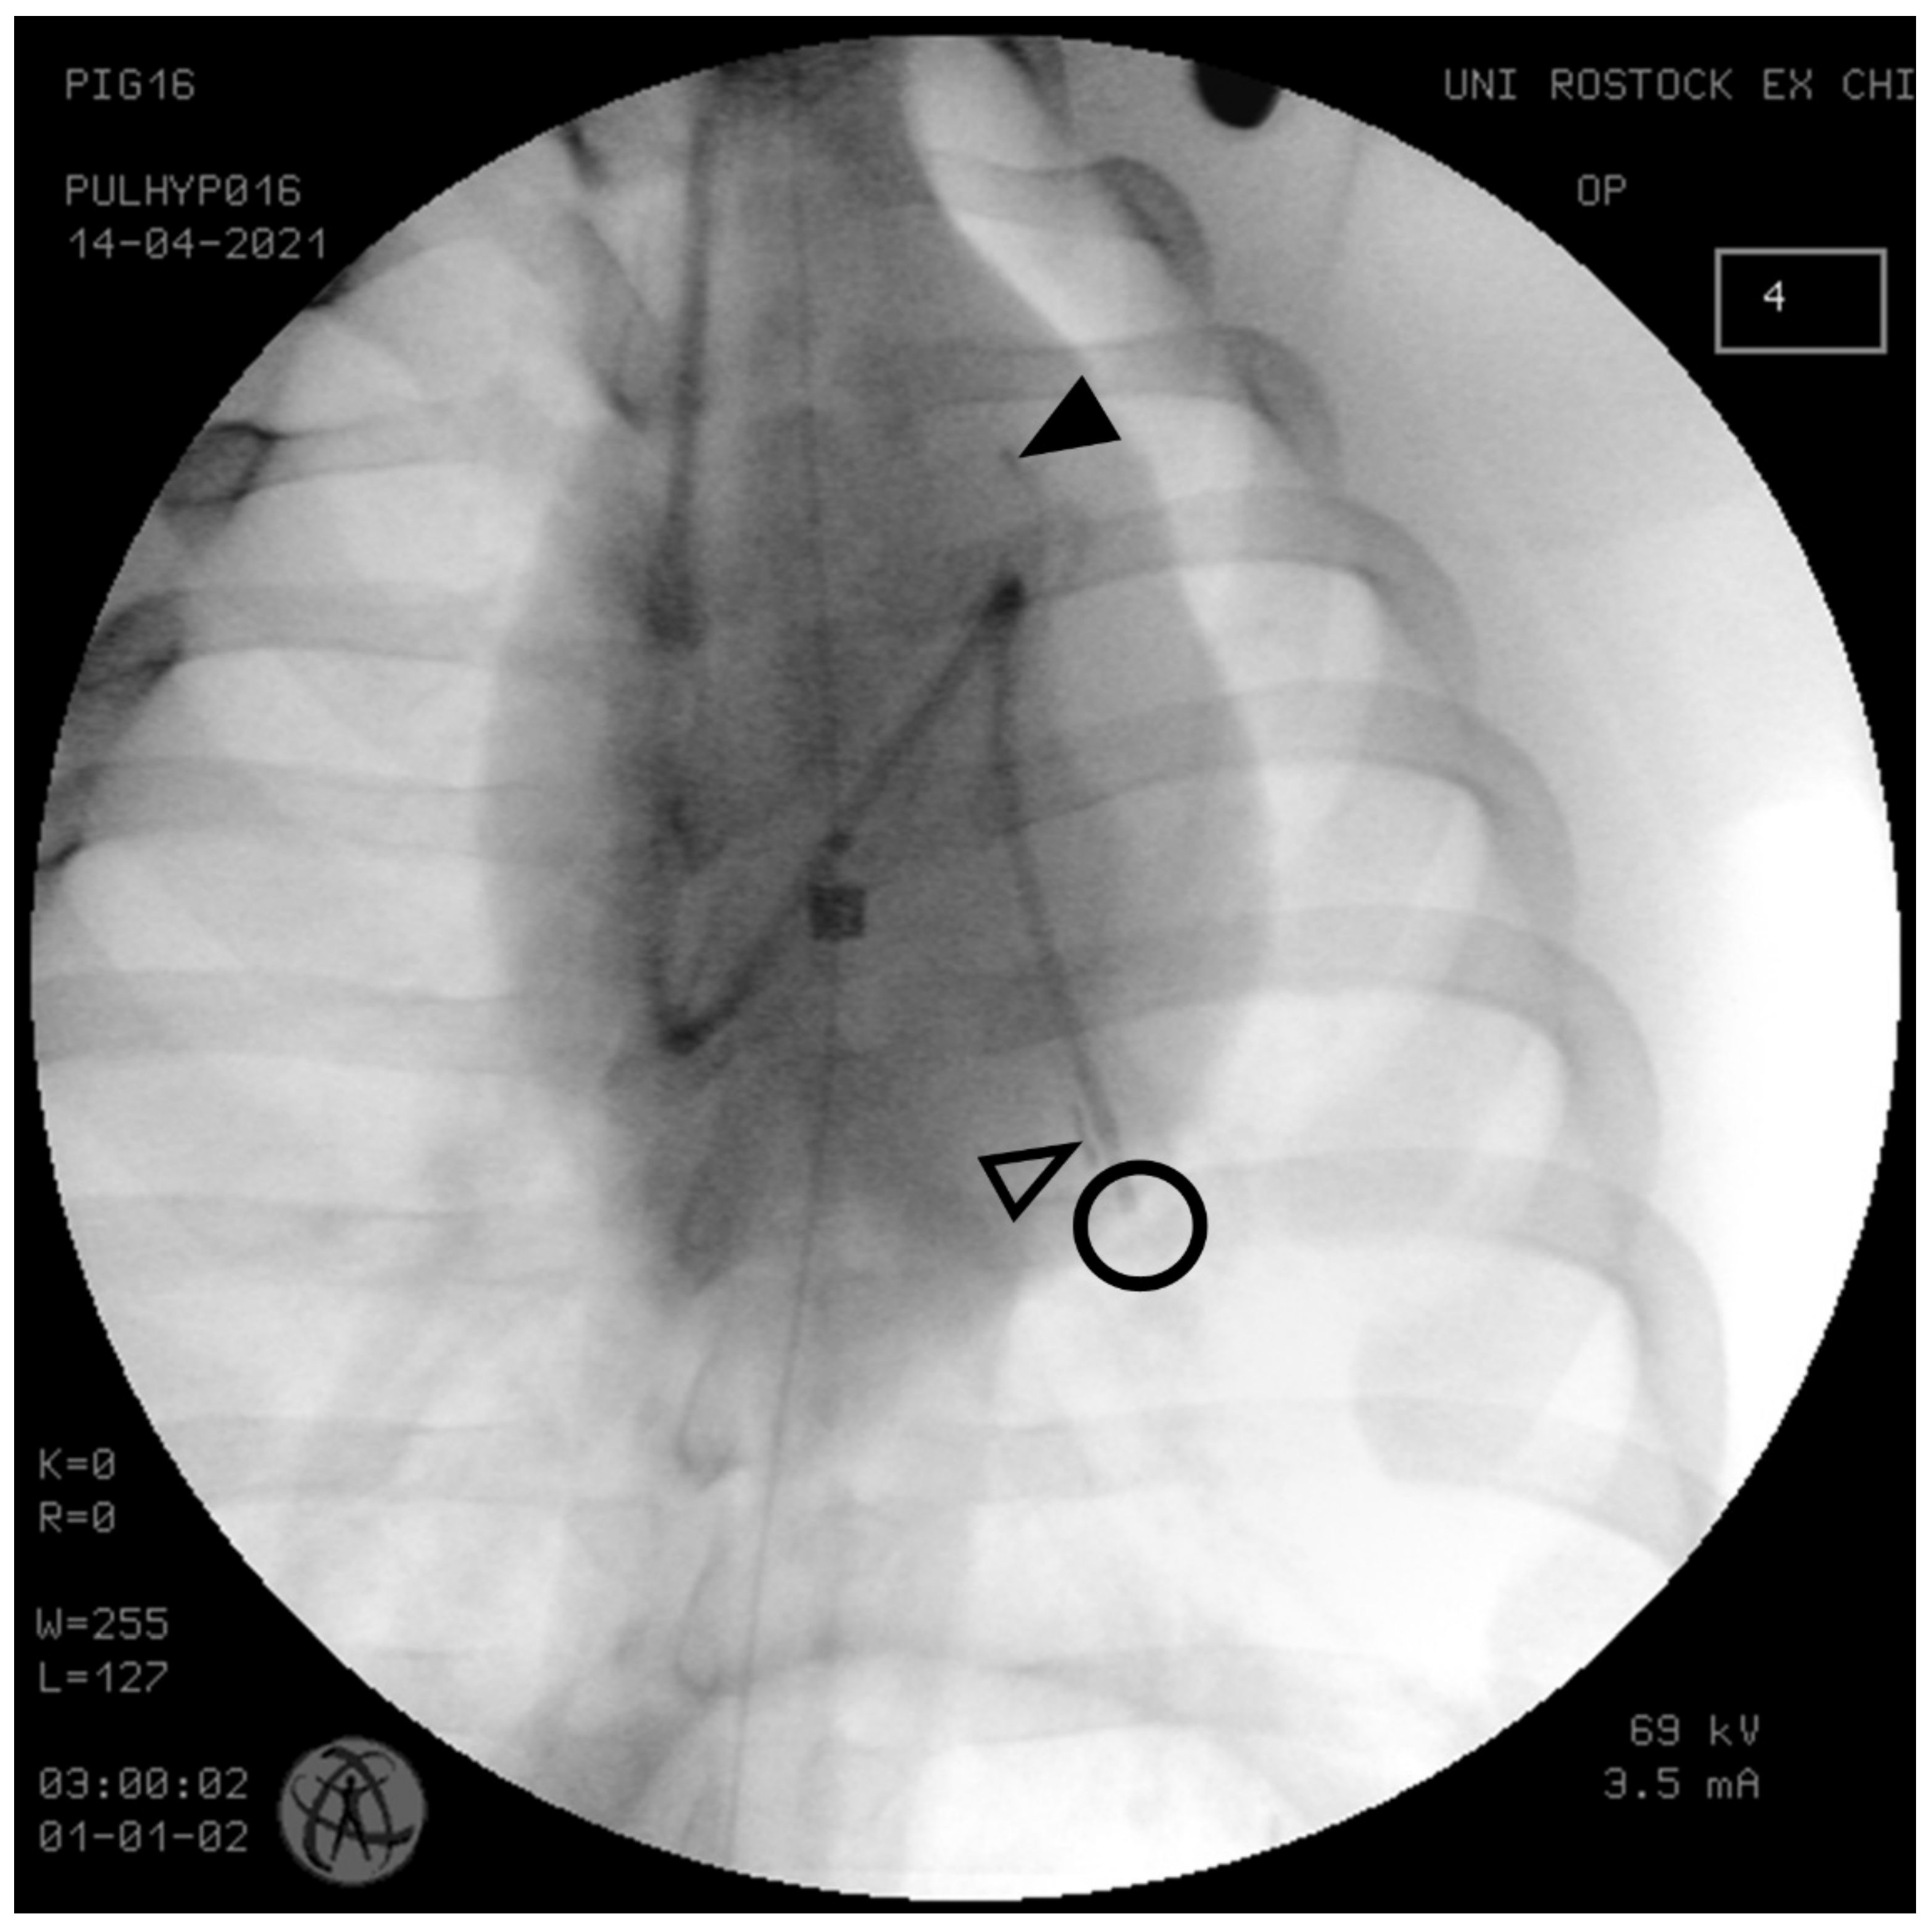

2.2. Instrumentation